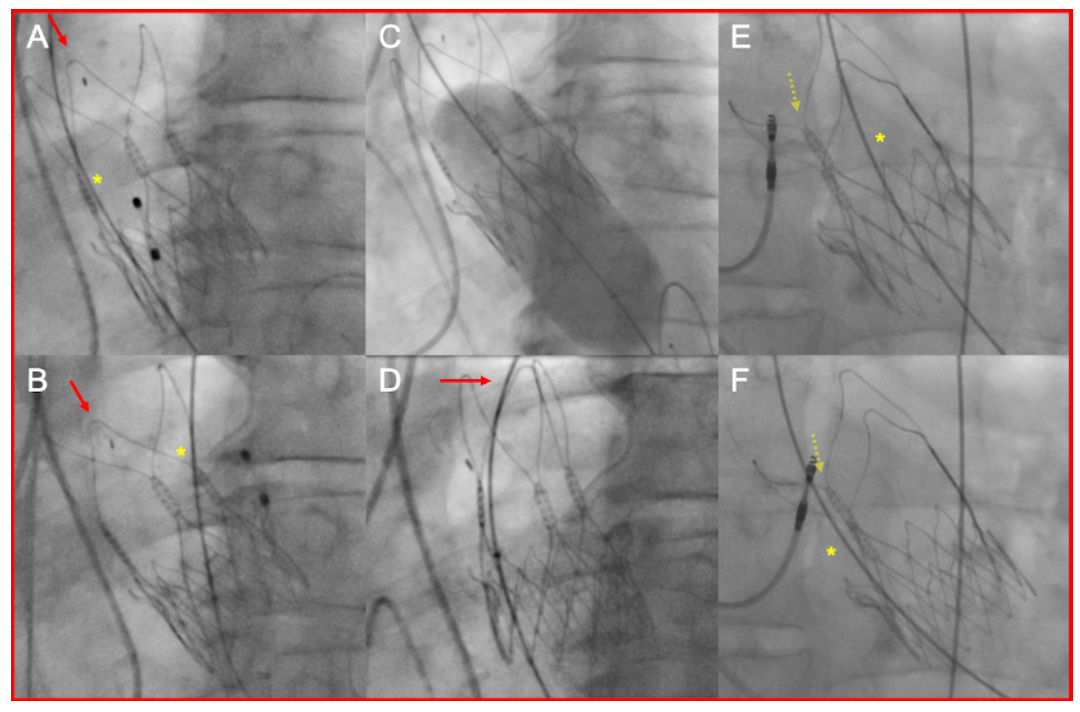

The 3 cases of device embolization that were associated with BPD occurred for various reasons, including capture failure during rapid ventricular pacing, retrieval of the preshaped stiff wire over the balloon catheter, and recrossing of the prosthesis with the balloon catheter via one of the stabilization arches, which caused dislodgment during retrieval of the deflated balloon (Figures 3A-3D). Even though capture failure during rapid ventricular pacing ultimately must be considered a fateful event,21 greatest care should be employed to achieve a stable position of the temporary pacing wire with reliable pacing thresholds. The risk of device embolization during retrieval of the preshaped stiff wire may be eliminated by exchanging the stiff wire over a pigtail catheter instead of using the balloon catheter.

Finally, to avoid unnecessary recrossing of the prosthesis, it is recommended to maintain transprosthetic access to the left ventricle unless the decision has been made regarding BPD.7 In the situation where the Acurate valve has to be recrossed (either due to inadvertent withdrawal of the wire or in staged procedures), a pigtail catheter should be used and placed at the top of the commissural posts for crossing. Thereafter, it is mandatory to confirm the correct wire position via fluoroscopy (Figures 3E, 3F). Any resistance when advancing the balloon should raise the suspicion of false recrossing and prompt verification of the wire position. A detailed review of cases revealed that THV damage associated with BPD may be commonly avoided with some precautionary measures.